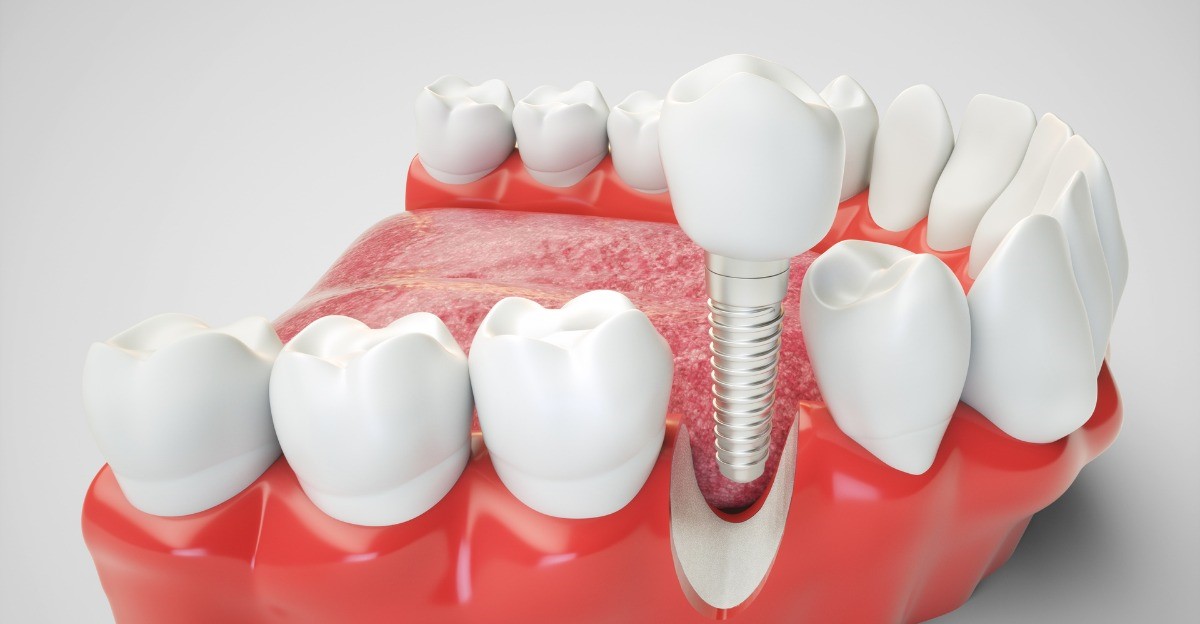

The placement of one or more dental implants involves risks. As with any dental, medical and surgical procedure, zero risk does not exist. Among the complications encountered we find…

The objective of any dental surgeon is to minimize the risks thanks to a preoperative study which will list the factors increasing the risks during dental implant placement The patient must be informed of all the risks and dangers inherent in an implantology operation although it is never possible to list them all. Below you will find a non-exhaustive list of the risks and the means to avoid or treat them.

The main risks of dental implants